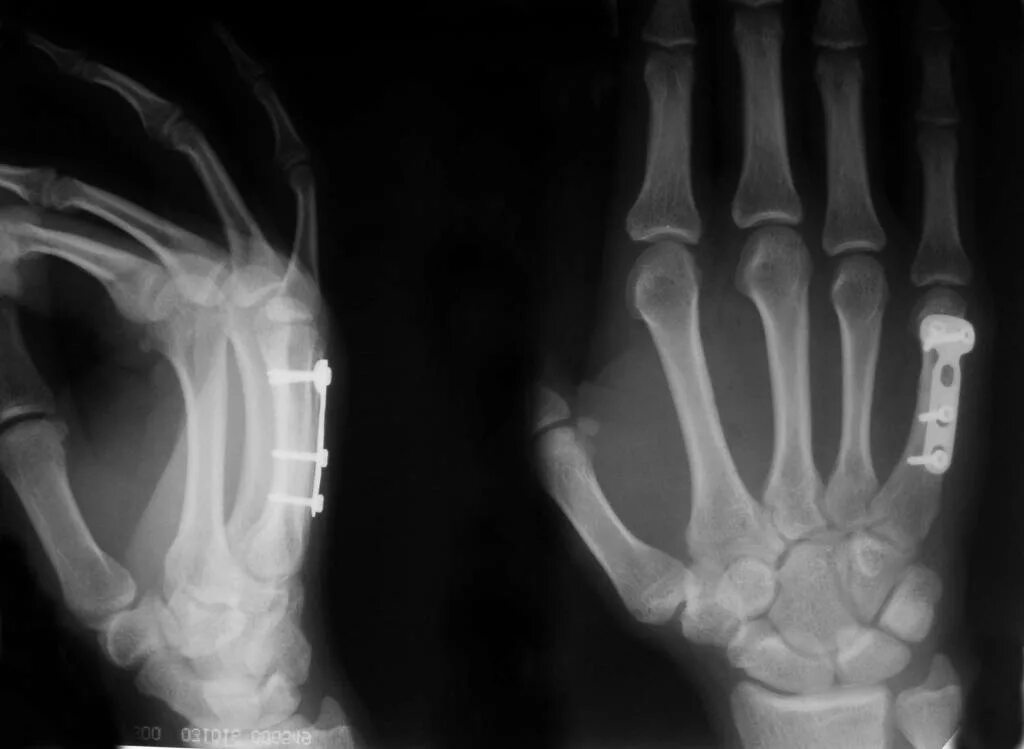

Перелом пятой пястной кости